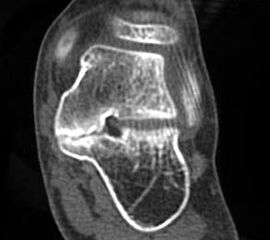

MRT und CT konkurrieren in der Fein-Darstellung der Knochenbrücke, der Beurteilung der nichtbetroffenen Anteile des Subtalargelenkes und der Sekundärveränderungen. Das MRT bietet den Vorzug, bindegewebige und knorpelige Strukturen (Abb. 2) und bei Einsatz von Kontrastmittel auch knöcherne Aktivierungsphänomene genau abzubilden; die knöcherne Feinstruktur und genaue Ausdehnung dagegen ist mit dem Dünnschicht-CT wesentlich exakter darstellbar (Abb.3). In manchen Fällen ist eine 3-D-Rekonstruktion des CT hilfreich. Besonders wichtig ist eine geeignete Schichtebenen-Wahl:

Die zweite wichtige Form tarsaler Coalitiones findet sich im medialen Bereich des Subtalargelenkes, am häufigsten unter Einbeziehung der medialen, mittleren Facette des talocalcanearen Gelenkes (Abb. 9). Die Ausdehnung der zunächst fibrösen, später zunehmend verknöcherten Brückenbildung kann sehr unterschiedlich Anteile der hinteren Kammer des unteren Sprunggelenkes mitumfassen; auch rein dorsomediale Formen ohne Einbeziehung der medialen Facette werden beobachtet (Abb. 2) 67 (Hamel 2008).

Diagnostisch sollte neben Röntgenübersichtsaufnahmen (indirekte radiologische Zeichen: Dorsaler Traktions-Osteophyt am Taluskopf, „talar beaking“; kontinuierliche Linie der Trochlea-tali-Kontur übergehend in die Sustentaculum-tali-Kontur, „C-Zeichen“ (Abb. 11) 10) immer die dreidimensionale Bildgebung eingesetzt werden. Das MRT (mit Kontrastmittel) kann die Struktur der Brückenbildung und z.B. die Qualität des Restgelenkes (Knorpel-Dicke) besonders gut abbilden; das Dünnschicht-CT zeigt die knöcherne Feinstruktur im Bereich der Coalitio und den oft sehr schrägen Spalt-Verlauf im Frontalschnitt dagegen häufig genauer. Meist findet sich die Überbrückung im Bereich der medialen Facette; die Schichten sollten jedoch bis weit nach dorsal beurteilt werden, da ansonsten dorsomediale Formen übersehen werden können. Rozansky et al 7 unterschieden fünf morphologische Typen auf der Basis von 3-D-CT-Rekonstruktionen. Allerdings ist eine prognostische Zuordnung bisher nicht möglich.